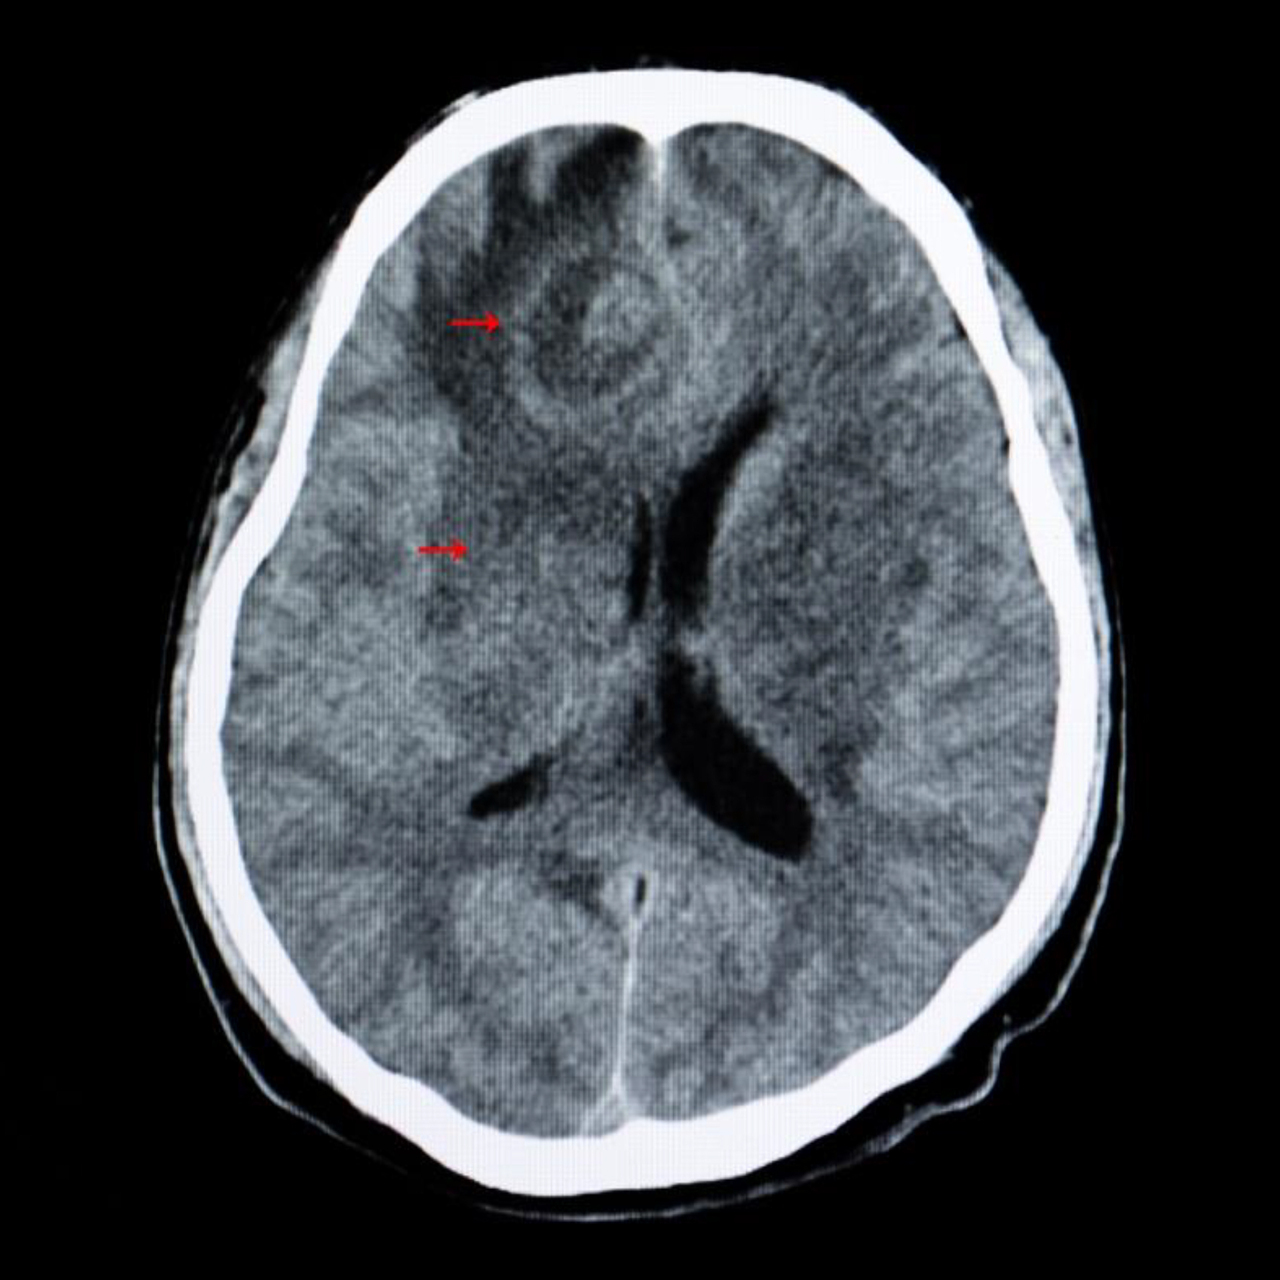

Le patient est transféré en urgence pour une TDM cérébrale afin de réaliser le bilan étiologique de son état de mal épileptique. Voici une coupe de la TDM cérébrale (figure 2). Figure 2 (Source : Adobe Stock)

Question 7 - Concernant cette coupe tomodensitométrique cérébrale, indiquez la (les) proposition(s) exacte(s) :

Pour les coupes d’imagerie, voici le vocabulaire : – axiale = transversale -> on voit le cerveau en étant au-dessus du patient ; – coronale = frontale -> on voit le cerveau en étant face au patient ; – sagittale -> on voit le cerveau en regardant le patient de côté. Ici on voit un rehaussement en périphérie de la lésion, la TDM est donc injectée. La zone hypodense autour de la lésion correspond à un œdème réactionnel à la lésion. On observe un effet de masse de la lésion sur le ventricule droit avec un engagement sous-falcoriel (glissement de l’hémisphère cérébral sous la faux du cerveau).

Question 8 - Parmi les pathologies suivantes, indiquez celle ou celles qui sont compatibles avec le tableau clinique et l’imagerie cérébrale du patient :

Devant une image cérébrale avec prise de contraste en cocarde (contour hyperdense et centre hypodense), il faut évoquer trois étiologies : – tumeur cérébrale ; – abcès cérébral ; – métastases cérébrales. La partie centrale est en fait nécrosée, c’est pour ça qu’elle ne prend pas le contraste. Les cancers solides qui donnent le plus de métastases cérébrales sont les cancers du sein, du poumon et le mélanome.